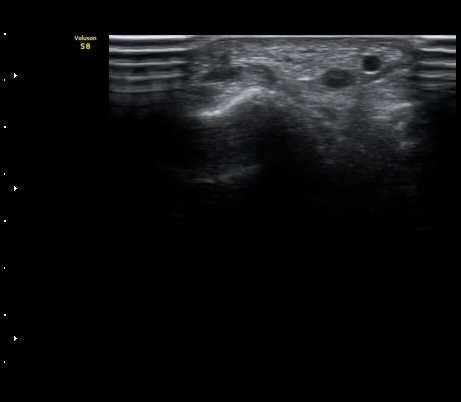

[ÆÈ²ÞÄ¡] ¿»ó ÈÄ ¹ß»ýÇÑ ¿ä°ñ½Å°æ ¸»´Ü °¨°¢½Å°æ ºÐÁö º´Áõ

ÃÊÀ½ÆÄ °Ë»ç